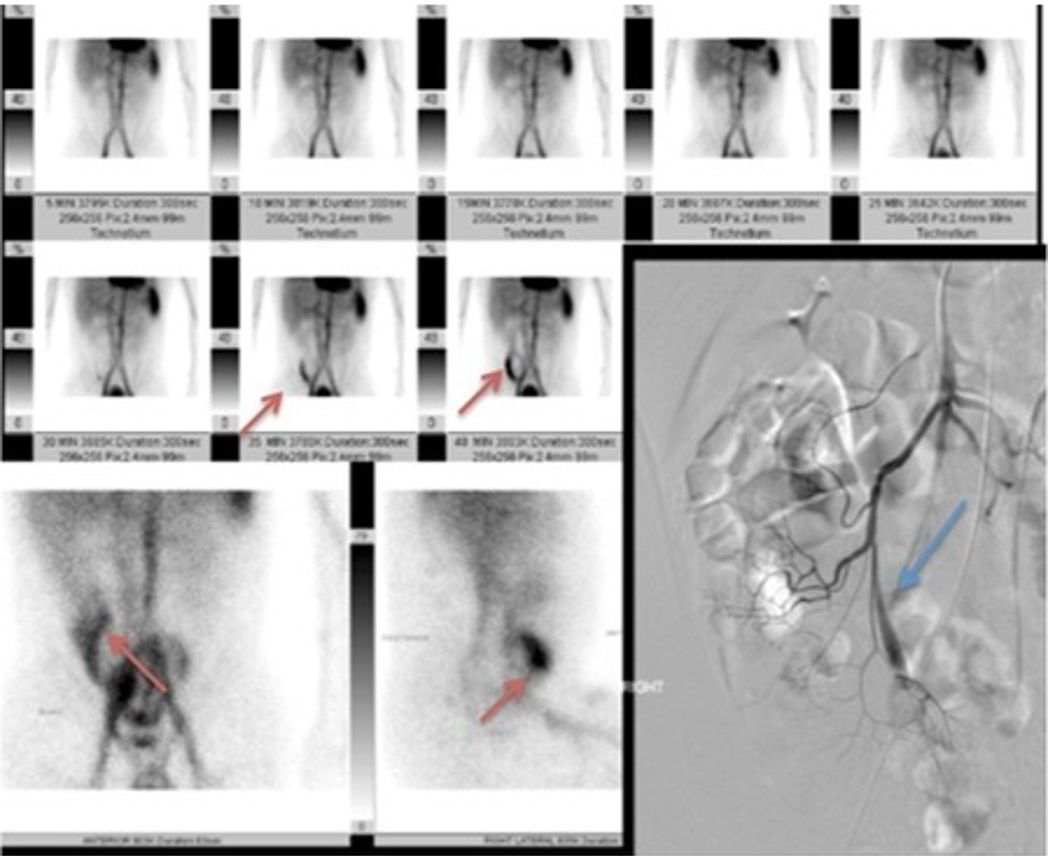

Vitelline artery (blue arrow)

Will typically be show in combo with Nuc med scan (tagged RBC) showing a Meckel diverticulum

persistent collection of radiotracer in the RLQ, WITHOUT movement through the GI tract

angiography shows a prominent vitelline artery

Meckel’s diverticula are a persistent outpouching due to periistent non involuting omphalomesenteric (vitelline) duct. 50% contain gastric mucosa